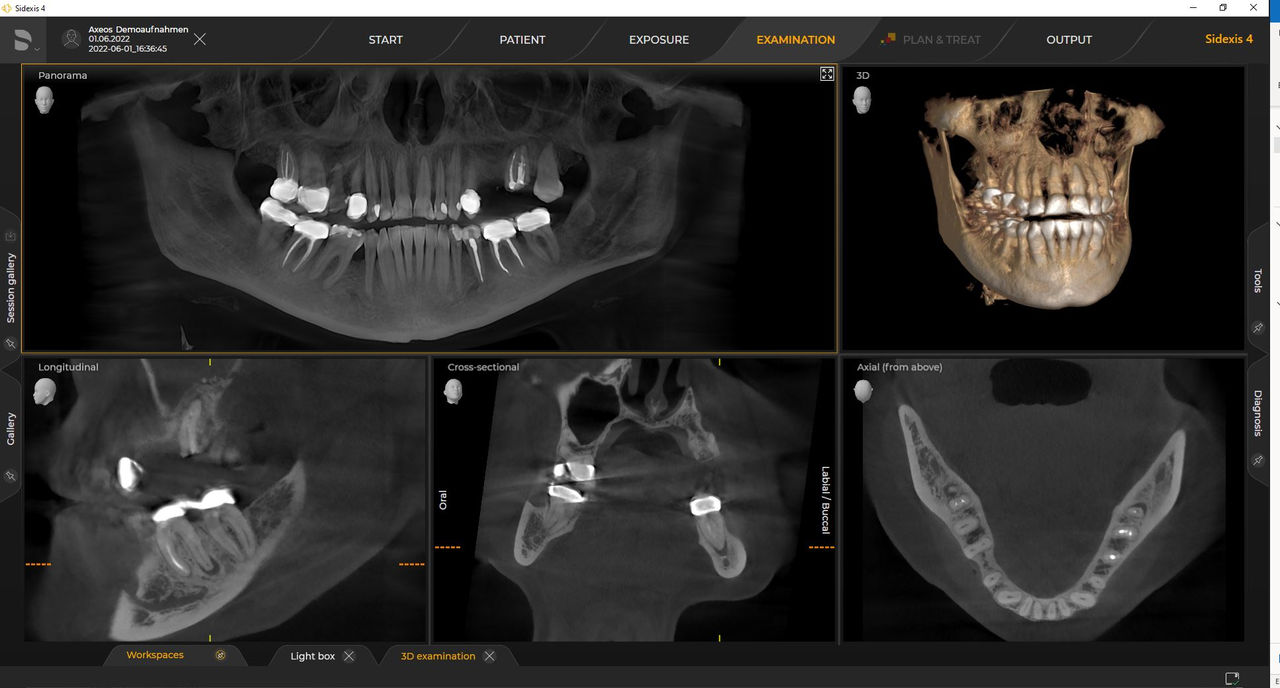

Axeos, el sistema especializado 2D/3D con un gran volumen y alta calidad de imagen para clínicas con una amplia oferta de tratamientos. Desarrollado junto a dentistas y clínicos, Axeos ofrece la gama más completa de funciones de todos los equipos de radiología extraoral de Dentsply Sirona. Además de una excelente calidad de imagen y tamaños de volumen 3D personalizados, el equipo de radiología dental está completamente optimizado para una mayor comodidad del paciente. Axeos no solo proporciona calidad en rendimiento y comodidad, sino también con su galardonado diseño gracias al cajetín de accesorios de bloque de mordida integrado y la luz ambiental.

Los numerosos tamaños de volumen garantizan la flexibilidad en la práctica diaria. Examine un área precisa o evalúe la dentición completa, lo que incluye las ATM

Las unidades 3D de Dentsply Sirona funcionan exclusivamente con Sidexis 4. Sin embargo, la migración de datos de Sidexis XG a Sidexis 4 es muy fácil. Sidexis 4 permite una experiencia digital completa con las últimas herramientas.